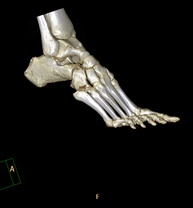

Exploració radiològica que mitjançant un sistema de raigs X i detectors que giren al voltant del pacient i que reconstrueixen les imatges per ordinador (TC Multidetector), permet l'estudi detallat dels ossos, els músculs i les articulacions del turmell i el peu. - TC d'estudi rotacional EEII (Bàscula rotuliana, distància TA-GT)